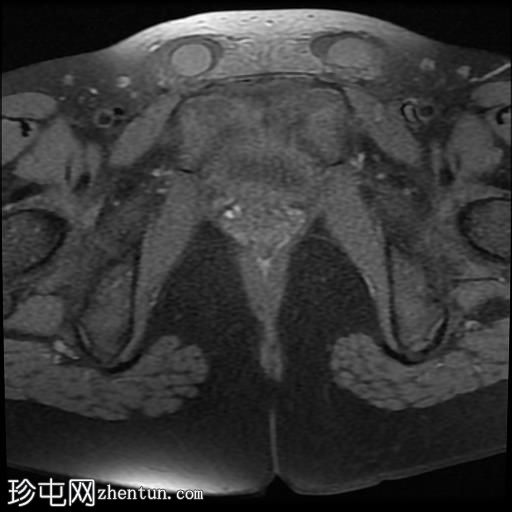

矢状位

T2加权像

脂肪抑制序列显示:

女性外生殖器

子宫、宫颈、阴道上2/3及卵巢缺失

双侧睾丸异位,沿腹股沟管清晰可见

MRI表现符合伴女性外生殖器的雄激素不敏感综合征(男性假两性畸形)。